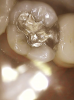

Fig 17. Pretreatment photograph, tooth No. 18 with large restoration.

Figure 17

Upon initial examination, Figure 17 and Figure 18 reveal a large restoration and potential problem on distal of tooth No. 18, though the clinician was uncertain about it. Once the CariVu was utilized, the clinician saw a fracture and complete degeneration of the distal buccal cusp (Figure 19), which fell apart when preparation began due to the severity of the fracture.